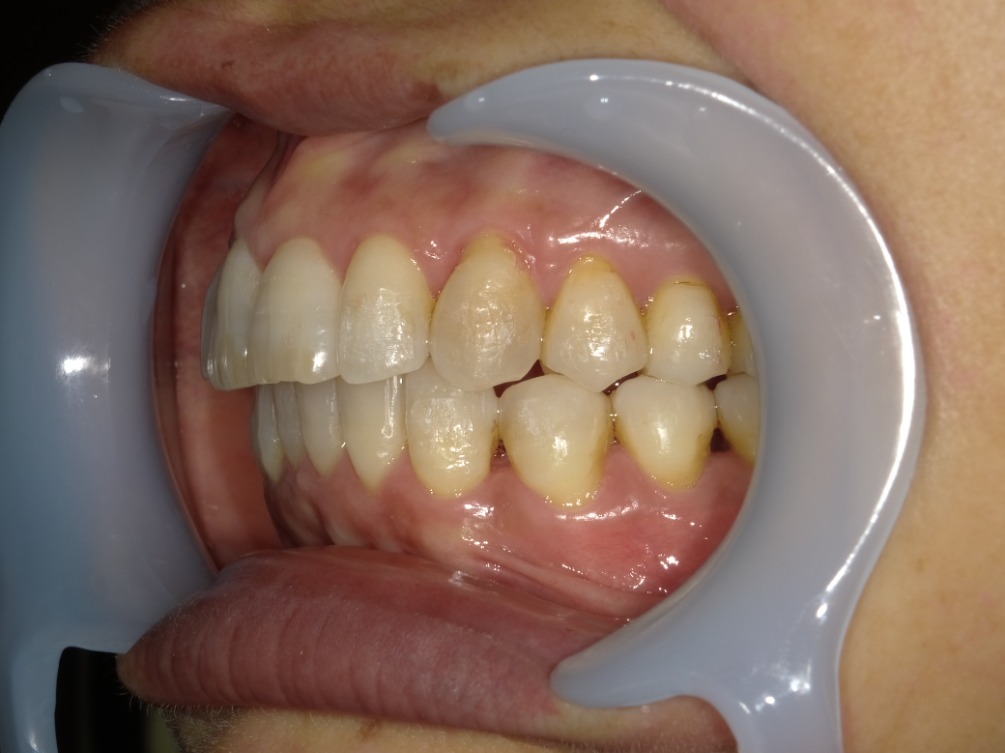

AFTER

左横